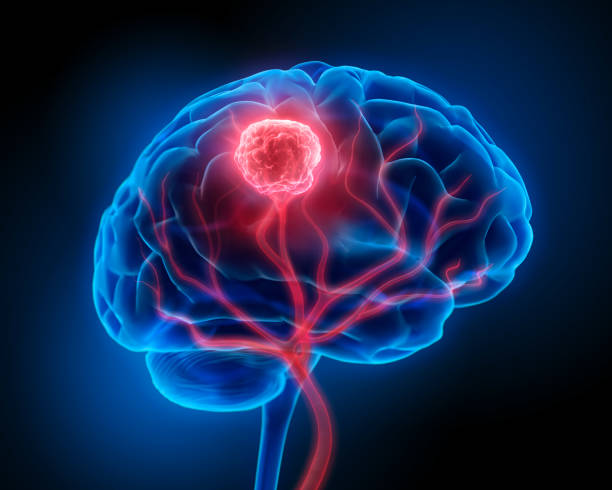

Brain tumor surgery is a specialized procedure performed to remove abnormal growths (tumors) in the brain. These tumors can be benign (non-cancerous) or malignant (cancerous). The primary goal is to safely remove as much of the tumor as possible while preserving normal brain function.

The procedure involves advanced imaging, careful surgical planning, and the use of modern techniques such as microsurgery and neuronavigation. Depending on the tumor type and location, the surgery may be performed using minimally invasive or traditional methods to ensure maximum safety and effectiveness.